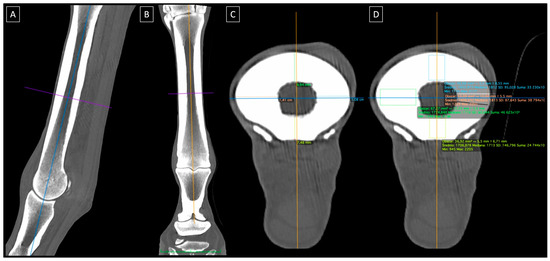

2.2. CT Imaging